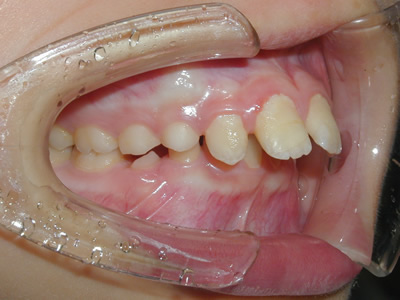

永久歯に交換するためのスペース不足による前歯のガタガタで、取り外しができる拡大床にて上下顎の幅を拡大した後、上顎の前歯をマルチブラケット装置で並べました。治療の期間は1年9か月でした。

初診時